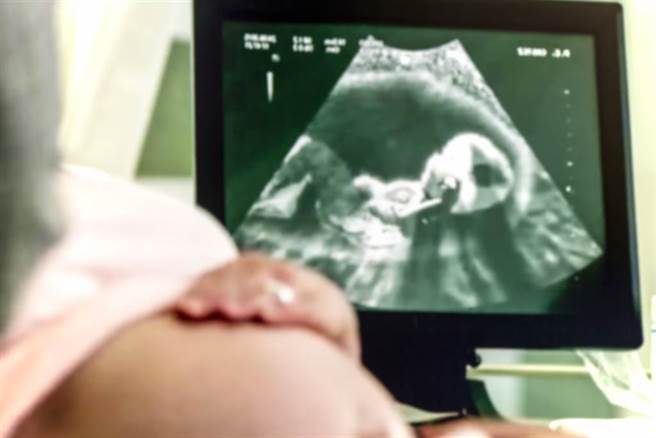

洁德提到,在大女儿出生前,她就曾流产过一次,而在二女儿出生后,她又再次流产,近日终于怀上第3胎,岂料在照超音波时,她发现影像中竟多出一张脸,起初让她感到有些震惊,「一开始我很害怕,但过了一会儿,我才慢慢安心,这张脸看起来像是一个婴儿,好像在一旁帮我看顾第3胎,我认为他是我先前流产的孩子」,

洁德描述,超音波影像中的人脸很清晰,可以看到他的眼睛、嘴唇和鼻子,她的朋友推测,洁德可能怀上双胞胎,但她再次做产检确认时,医师证实她的肚子里只有一个婴儿,洁德提到,「当我的女儿看到超音波里的那张脸时,她们当下非常害怕,到现在依旧不敢再看照片第2次」。